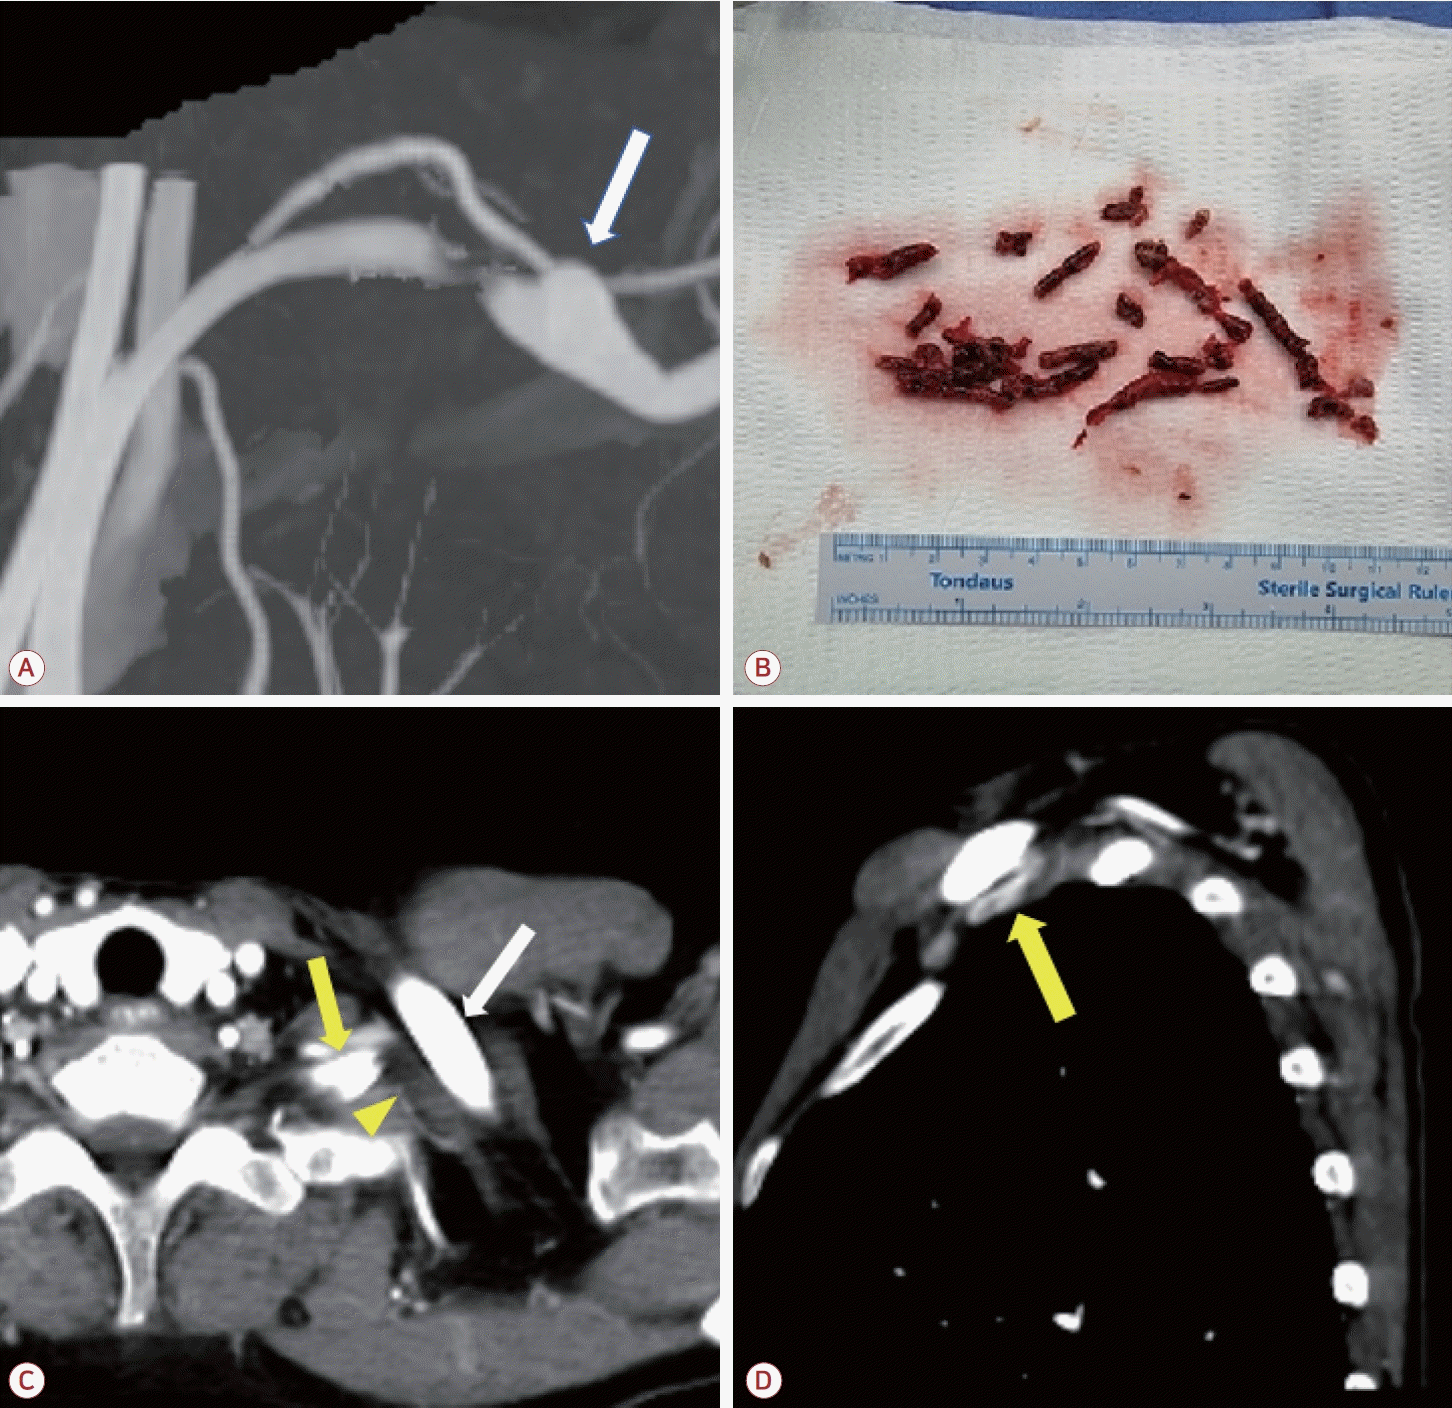

뇌자기공명영상의 확산강조영상(diffusion-weighted image) 에서는 우측 소뇌 및 소뇌다리, 좌측 후두엽에서 다발색전 양상의 고신호강도 병변이 보였다(Fig. 1-A). 또한 이후 시행한 뇌전산화단층촬영 혈관조영영상에서는 우측 척추동맥의 형성 저하 외에는 뇌내혈관 및 경동맥의 유의미한 협착은 관찰되지 않았다(Fig. 1-B). 또한 상지 전산화단층촬영혈관조영에서 쇄골하동맥의 폐색이 관찰되었으며(Fig. 1-C) 우측에 비해 좌측 쇄골과 경추늑골 사이 공간이 협소하고 혈류가 감소한 소견이 보였다(Fig 1-D, E). 혈액 검사상 D-이합체(D-dimer)는 3.21 μg/mL (정상, 0.0-0.5)로 상승되어 있었으며 항인지질인자, C/S단백질(protein C/S), 항트롬빈-III, 폰빌레브란트인자 등의 검사는 별도로 진행하지 않았다. 심전도, 경흉부 및 경식도심초음파, 24시간심전도 검사에서 심인성 색전증을 일으킬 수 있는 다른 질환은 발견되지 않았다.

Figure 1.

Magnetic resonance imaging and computed tomographic angiography on admission. (A) Diffusion weighted imaging showing acute multiple embolic infarctions of the right cerebellum, cerebellar peduncle, and left posterior lobe. (B) Intracranial computed tomography (CT) angiography. No remarkable abnormal findings except hypoplastic right vertebral artery. (C) Reconstruction of upper extremity CT angiography on the second day of admission showing occlusion of the left brachial artery just after the origin of the left vertebral artery (yellow arrow). (D, E) Sagittal view of upper extremity CT showing the subclavian artery. Luminal narrowing with absent blood flow and thrombosis on the left side versus patent artery (red arrow) between the clavicle and accessory rib on the right side (white arrow).